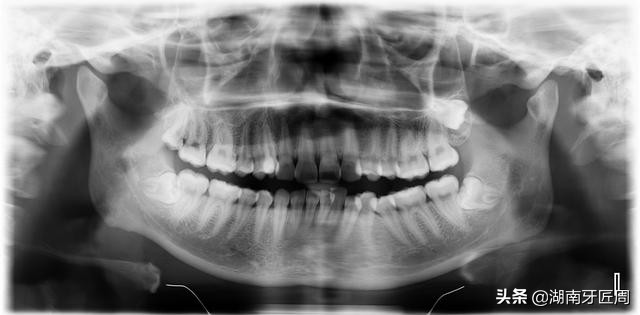

牙科全景片

牙片主要有全景片(大片)和根尖片(小片)和头颅侧位片,必要时可做口腔科电子计算机X线体层摄影(CBCT)辅助检查。

牙齿在牙片上显示出白色阻射影像,牙釉质阻射最强,牙本质和牙骨质阻射低于牙釉质,牙髓腔呈黑色透明影像,根管口至根尖孔呈逐渐变细的影像。